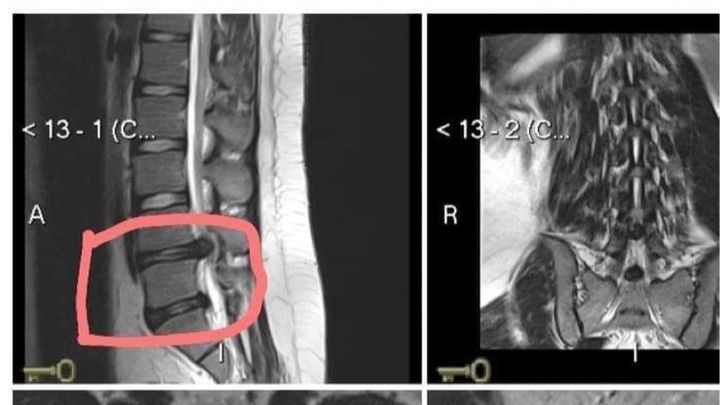

Ricardo is 16 years old. While taking a shower, he slipped and fell on the concrete so hard that he hurt his back. At first, he thought little of it and tried to recover at home. This happened about a month ago. In Mexico, getting medical intervention can get very expensive and it seemed easier to Ricardo to just try to get better with rest. Recently, his pain became more excruciating. His family thought that with more rest, he would get better, but when Ricardo suddenly was unable to move, his family was terrified. Ricardo's father took him to the hospital where the doctor diagnosed him with spinal injuries including subligamentous disc extrusion L4-L5, displacement of the nerve roots of the medullary sac, disc protrusion L5-S1, discopathy L4-L5 and L5-S1 Grade IV Pfirrman classification ( a total of 5 grades, thus, a very bad injury), and mild facet synovitis.